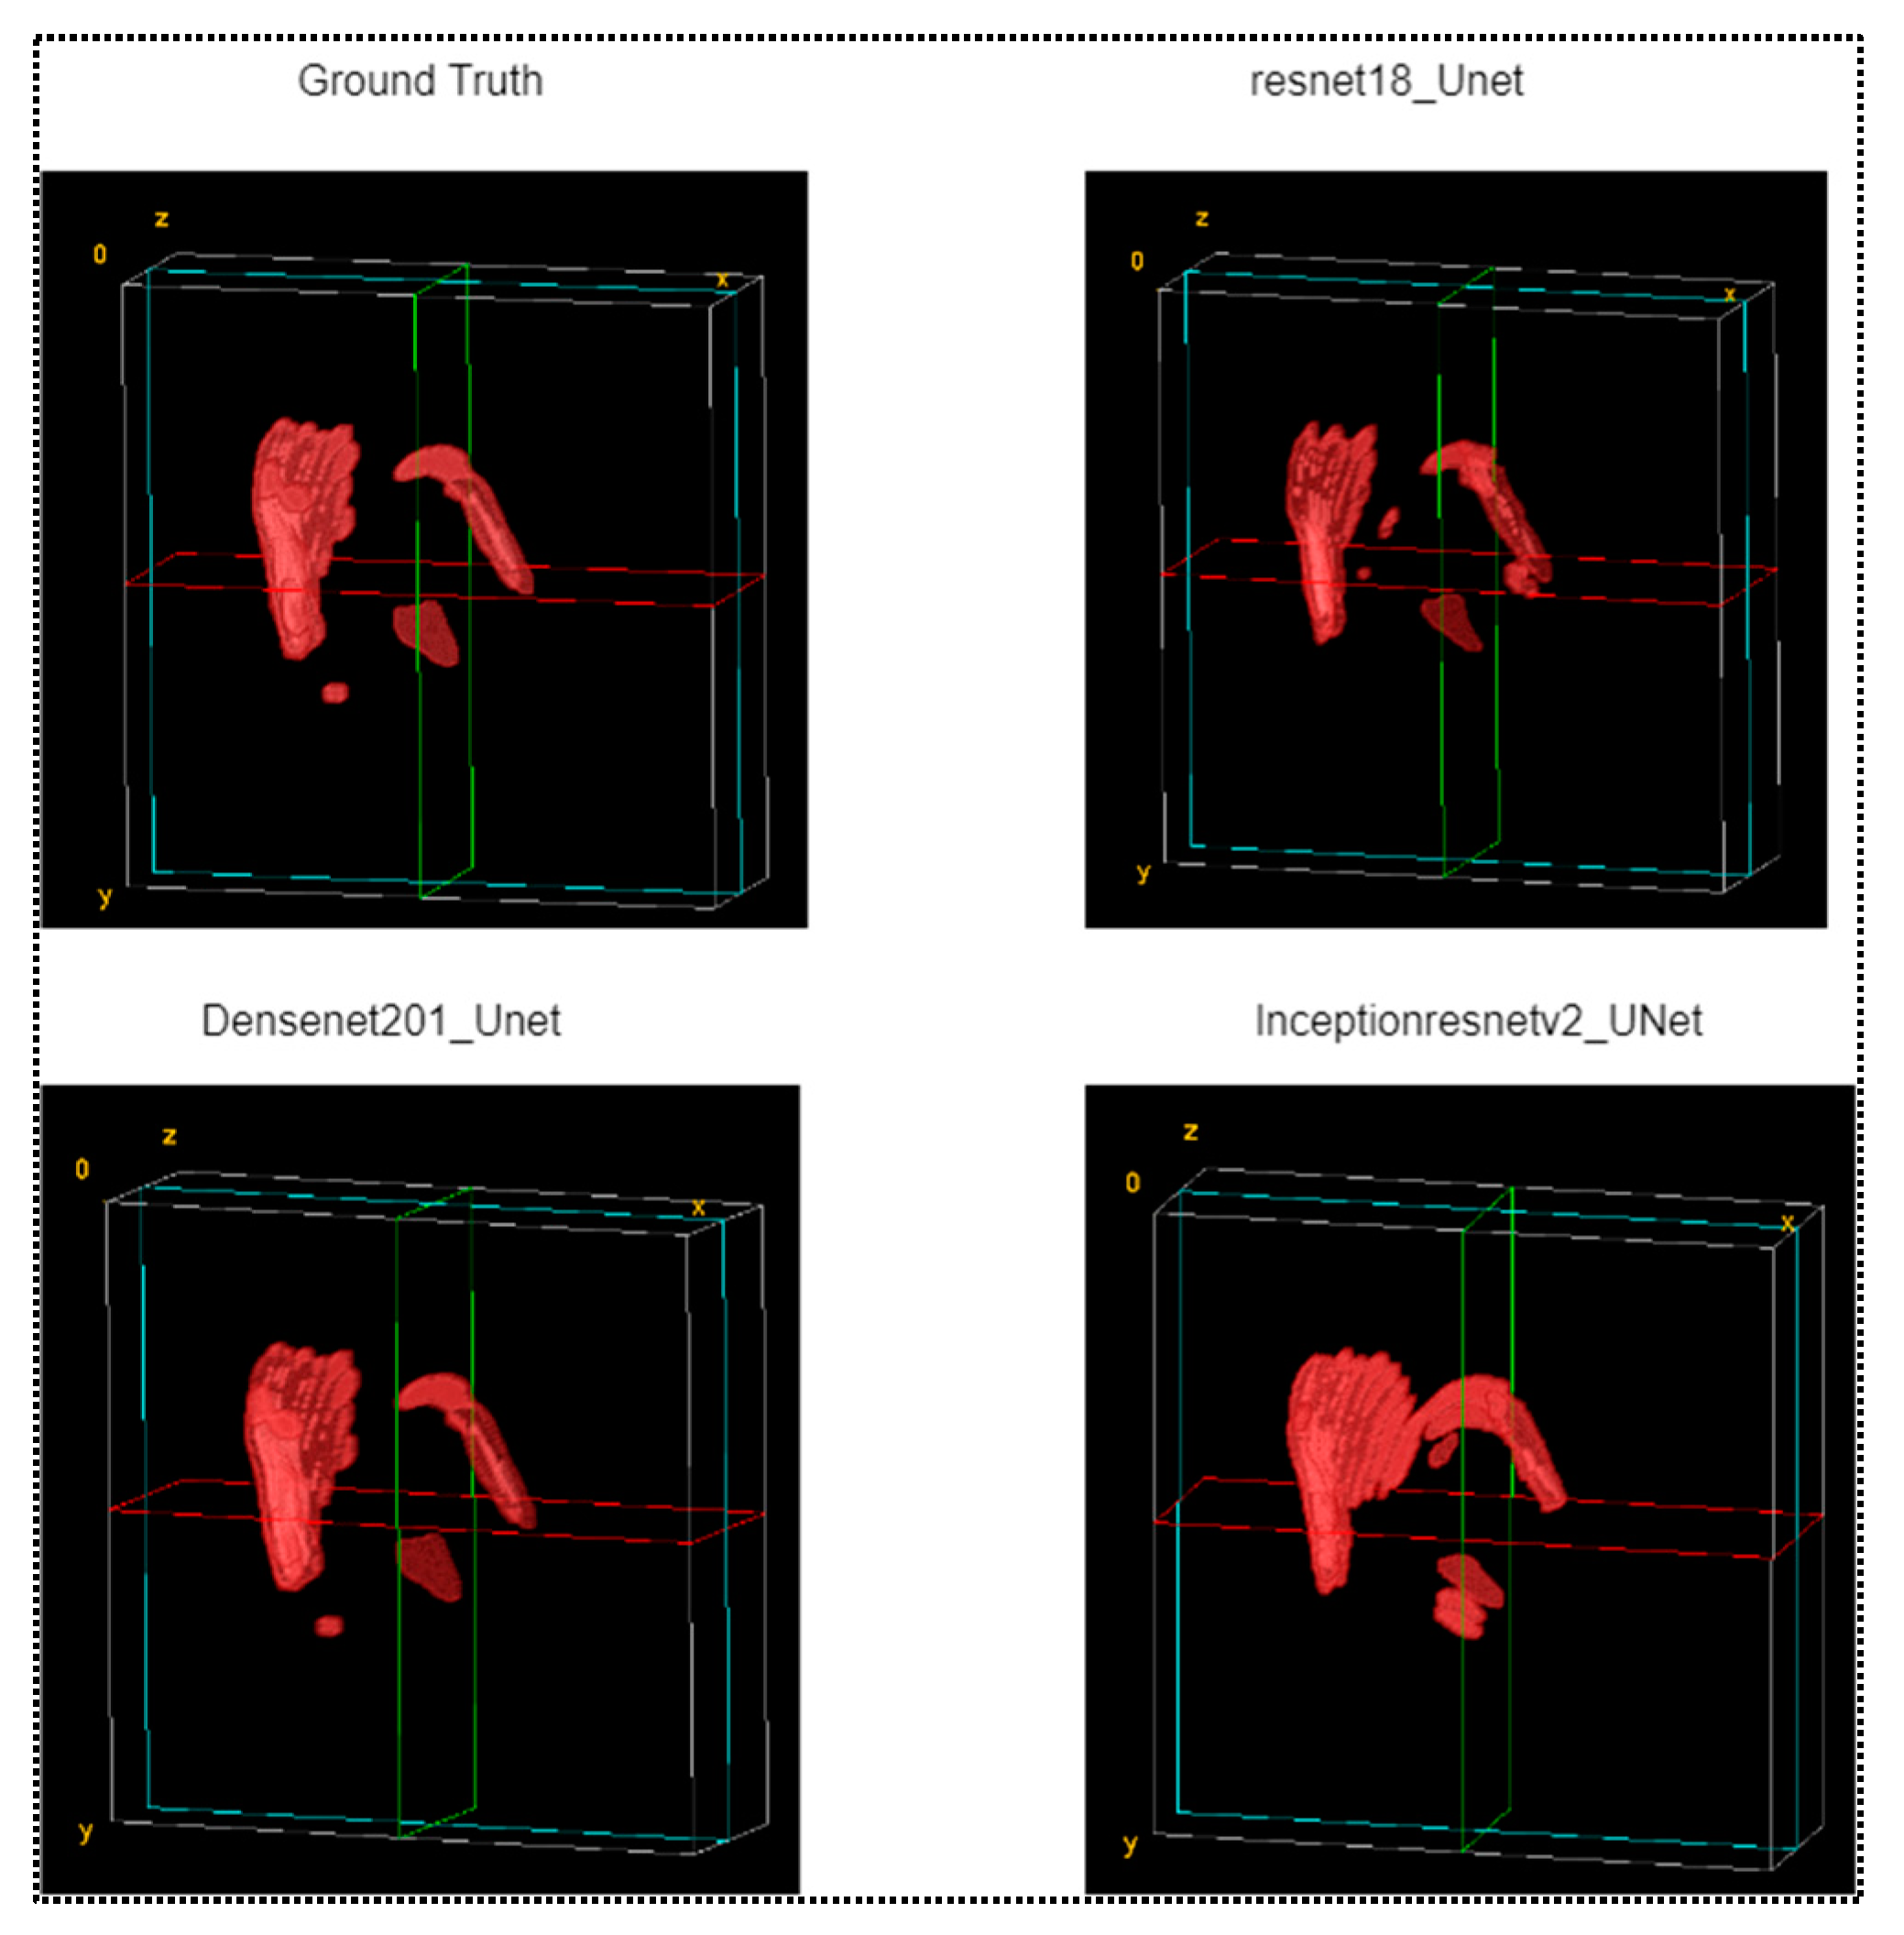

- This work presented a 3D visualization tool to show the hemorrhage in the CT volume predicted using the proposed technique and compare it with a ground truth hemorrhage annotated by the experts.

3.2. Reconstruction of 3D Models of ICH

3.3. Volume Measurement of Intracranial Hematoma